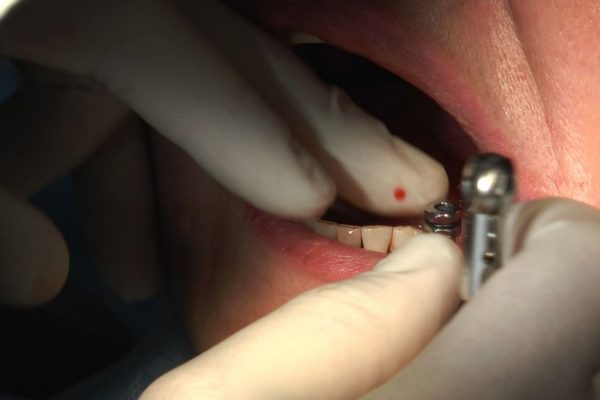

W ostatni weekend czerwca 2018 roku kursanci II Sezonu Preludium Implantologii odbyli piątą, finałową sesję, która w całości podporządkowana była praktyce. W ciągu dwóch dni zabiegowych Lekarze uczestniczący w szkoleniu przeprowadzili szereg zabiegów pod kierunkiem dr n.med. Violetty Szycik. Wszczepili 17 implantów oraz przeprowadzili ekstrakcje i zabiegi regeneracyjne kości. Zabiegi były wykonywane także w sedacji dożylnej z udziałem specjalisty anestezjologii i intensywnej terapii dr Jolanty Grzybowskiej. Preludium implantologii to nowy program edukacyjny dla adeptów implantologii stomatologicznej, którego celem jest wprowadzenie do implantologii poprzez pozyskanie wiedzy w szerokim zakresie i uwzględnieniem szczegółów mających decydujące znaczenie dla powodzenia leczenia implantologicznego. Ale tak jak wszystkie szkolenia w Instytucie Vivadental, w tym wiodące Practiculum Implantologii, zorientowane jest na praktyce i samodzielnym wykonywaniu zabiegów pod kierunkiem Mentora. To najlepsza edukacja w medycynie zabiegowej, a zarazem najlepszy start do implantologii.